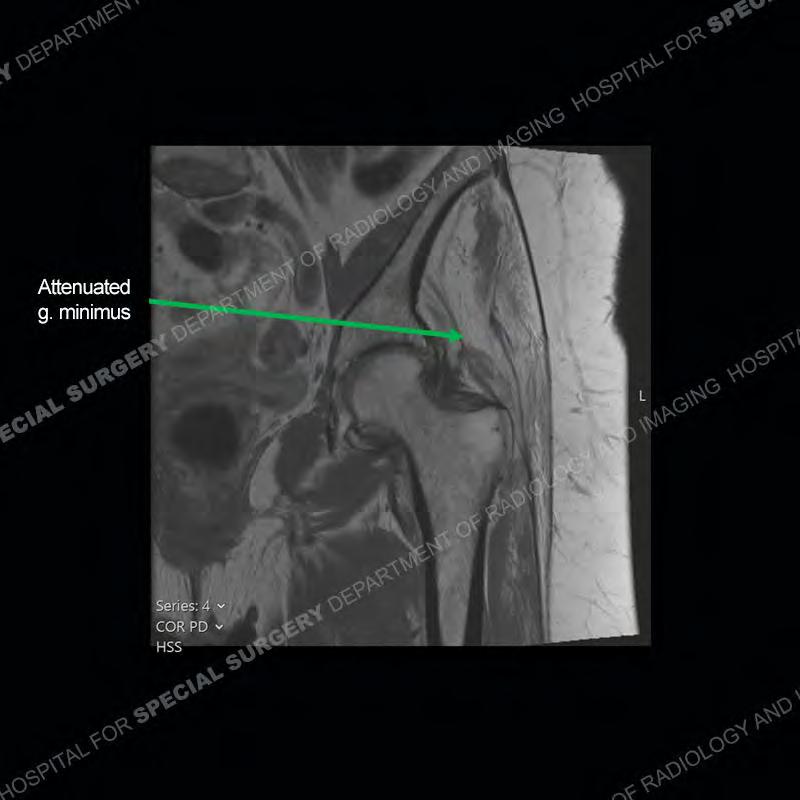

The radiograph is not particularly contributory in this case. The MRI demonstrates markedly abnormal architecture of the gluteus minimus and anterolateral band of the gluteus medius. Portions of the tendons are high signal, portions are highly attenuated, and portions are disrupted. A large, complex fluid collection is present in the adjacent soft tissue.

Not as much of a diagnostic dilemma as many of the other cases shown but just a nice example of the pathology seen of the gluteal tendons and a cause of trochanteric pain. Although, frequently thought of in isolation, trochanteric bursitis or bursal thickening is much more commonly a reactive change to underlying pathology of the subjacent gluteal tendons. The gluteus medius is divided into a posterior band and an anterolateral band. Tendinosis and partial tearing very commonly will involve the gluteus minimus and especially the more posterior fibers and then propagate into the anterior lateral band of the gluteus medius. Involvement of the posterior band of the medius is much less common and engenders a marked degree of functional impairment.

The bursae about the greater trochanter can be a little bit confusing especially given the terminology. Trochanteric bursitis is implied to mean the subgluteus maximus bursa which is present deep to the maximus and just lateral/superficial to the trochanter. That is the bursa involved in this case. In this case the complexity of the bursa relates to the tendon tearing with inflammatory change and probably hemorrhage accounting for the complexity. Two other, less frequently involved bursa are also present. The subgluteus medius and subgluteus minimus bursa are found just deep to the named tendons. Although pathology does frequently follow the previously described pattern it is possible to have isolated pathology to either the medius or minimus.